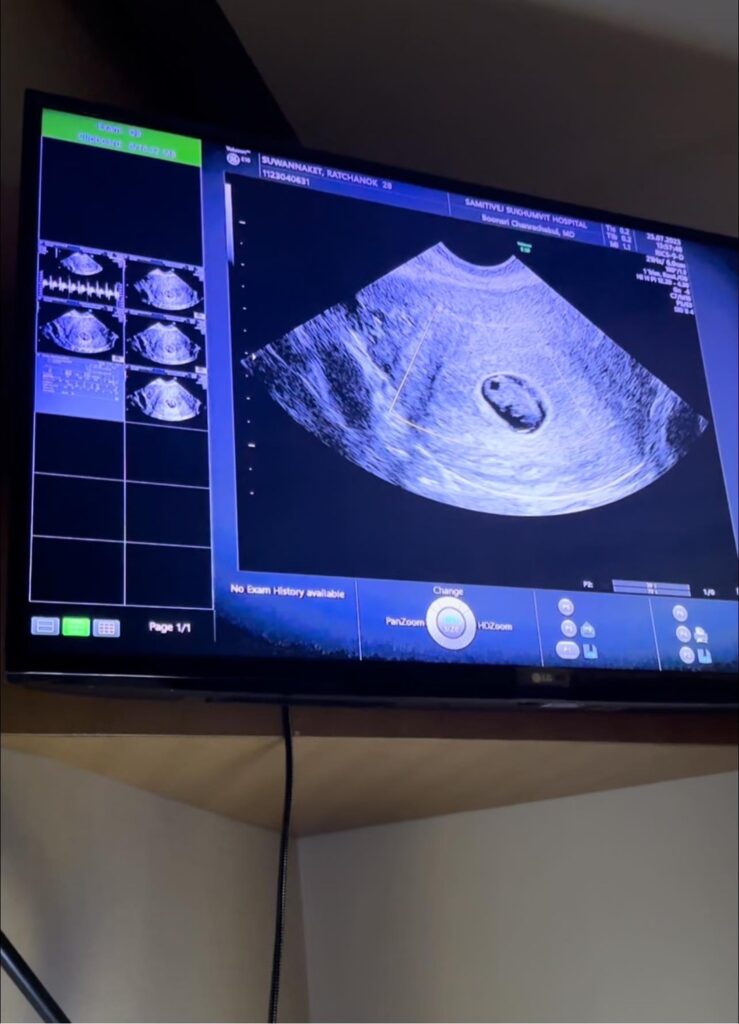

ขออนุญาตใช้พื้นที่ตรงนี้แชร์ประสบการณ์สั้นๆให้ฟังนะคะ อย่างที่ทุกคนทราบกันว่าเจนนี่ได้ตั้งครรภ์มีลูกคนที่ 2 เจนนี่ตรวจเจอน้องเมื่อต้นเดือนที่ผ่านมา จนกระทั่งน้องอายุครรภ์ได้ 7 วีคกว่าๆ เจนนี่มีเลือดไหลบริเวณช่องคลอด จึงได้ไปหาลุงหมอ ลุงหมอตรวจอัลตร้าซาวด์น้องหัวใจเต้นปกติ อยู่ในบริเวณมดลูกปกติ แต่คุณหมอบอกว่ามีเลือดไหลเยอะกว่าปกติ จึงให้เจนนี่ฉีดยากันแท้ง มีสั่งยากลับบ้านให้เจนนี่สอดยาเช้าเย็นทุกวัน รวมถึงกินยาฮอร์โมนวันละ 3 เวลา เพื่อเพิ่มฮอร์โมนในรังไข่ เพราะคุณหมอบอกว่าสาเหตุของการมีเลือดไหล อาจจะมาจากฮอร์โมนไม่เพียงพอ หรืออีกสาเหตุคือน้องไม่สมบูรณ์ คุณหมอก็มีบอกให้ทำใจไว้บ้าง เพราะเคสแบบนี้เจอเยอะมากๆ หลังจากนั้นเจนนี่ก็กลับบ้านมา กินยา สอดยาตามหมอสั่ง ผ่านไปสักระยะ เลือดมีไหลมากขึ้นและเจนนี่มีอาการปวดท้องน้อย เจนนี่จึงได้โทรนัดตรวจกับป้าหมออีก รพ เพื่อความชัวร์ ตรวจหลายๆที่เพื่อความสบายใจ จนกระทั่งวันนี้ที่เจนนี่ได้ทำการอัลตราซาวด์ครั้งที่สอง ปรากฎว่าป้าหมอไม่เจอหัวใจของน้องแล้ว ( ป้าหมอพูดไม่ทันจบป๊ายิวก็ร้องไห้แล้วเดินออกไปจากห้องตรวจ ) มดลูกของเจนนี่ไม่มีแผล ไม่มีอาการผิดปกติ แต่สาเหตุมาจากน้องไม่สมบูรณ์ เคสแบบนี้ถือเป็นการคัดเลือกแบบธรรมชาติ เปรียบเสมือนการปลูกเมล็ดถั่ว บางเมล็ดสามารถเติบโตได้ บางเมล็ดไม่สามารถเติบโตได้ วินาทีนั้นช่างบีบหัวใจจริงๆ ต่อให้เราทำใจมาบ้างแล้ว เมื่อถึงเวลาก็รับไม่ไหวอยู่ดี หลังจากทราบอาการและรายละเอียดต่างๆ คุณหมอจึงได้มีการนัดขูดมดลูกในวันพรุ่งนี้ค่ะ เจนนี่ขอบคุณทุกกำลังใจที่ส่งเข้ามานะคะ เรื่องแบบนี้ทำใจยอมรับได้ยากมากๆจริงๆ แม่ขอให้ลูกโชคดีนะตัวเล็ก ไว้กลับมาหาแม่ใหม่ในวันที่หนูพร้อมนะ รู้มั๊ยป๊าเค้าร้องไห้ทุกครั้งที่คิดถึงหนูเลยนะ หลังจากแม่เสร็จภารกิจ แม่กับป๊าจะทำบุญไปให้นะลูกรัก 😞